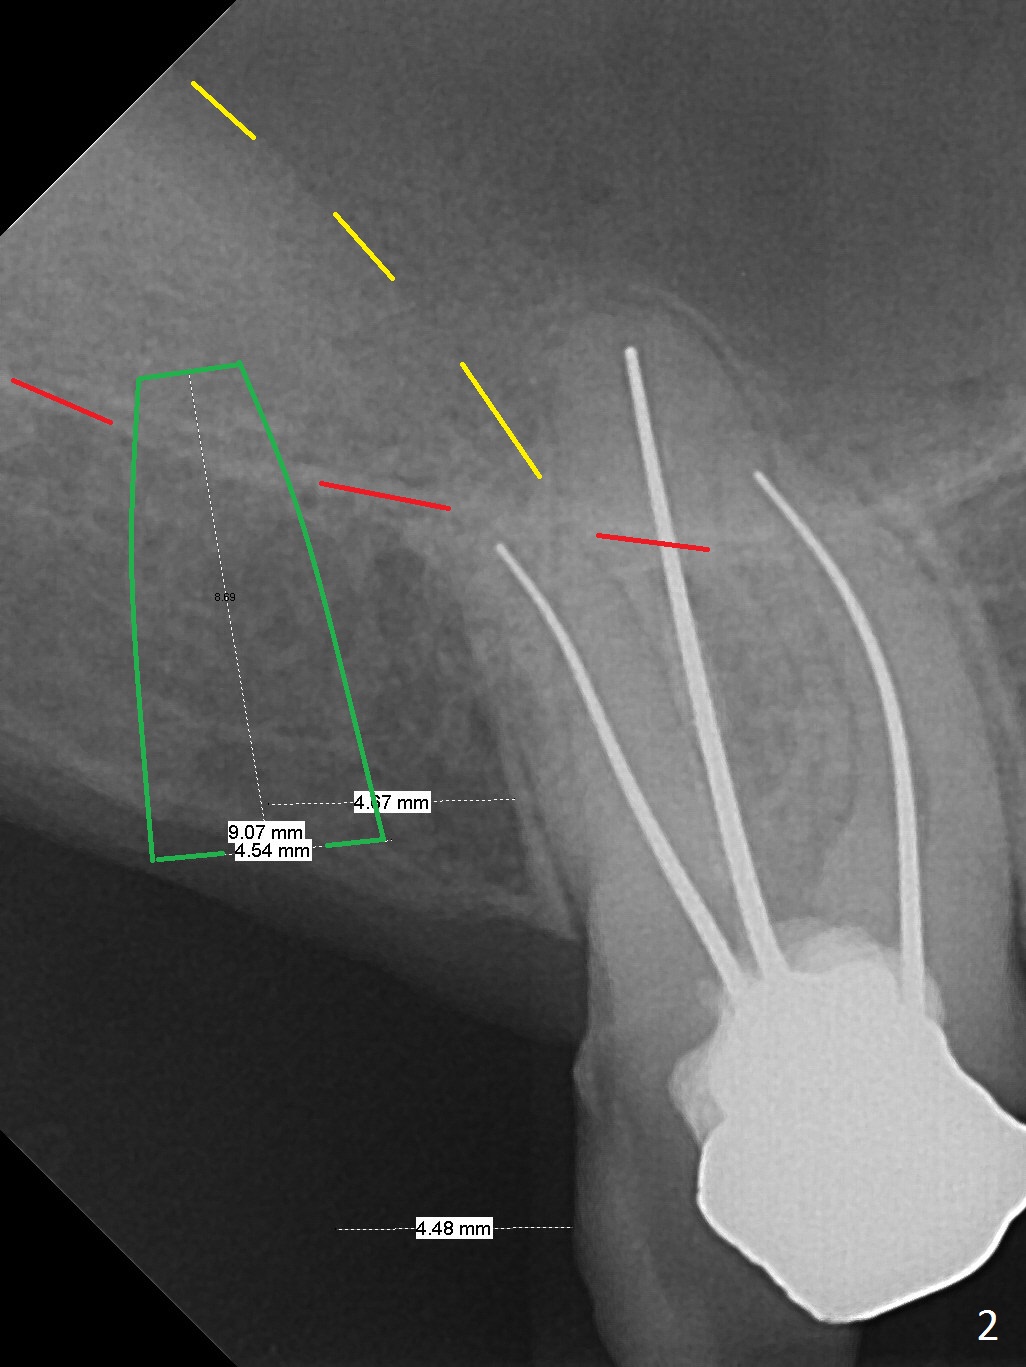

A 59-year-old man had #2 extracted approximately 4 months earlier (Fig.1 pink: possible buccal sockets; blue: palatal one). The edentulous ridge seems to be wide with exostosis (Fig.2 yellow line). Use Magic Split for access and initial bone expansion, followed by Magic expanders. The initial depth will be 7 mm to avoid sinus membrane perforation. Place PRF membranes and bone graft prior to inserting a 4 mm dummy implant. Periodontal dressing may be applied to the rugged surface of the tooth #3 for increased retention. Or a splinted provisional will be fabricated.